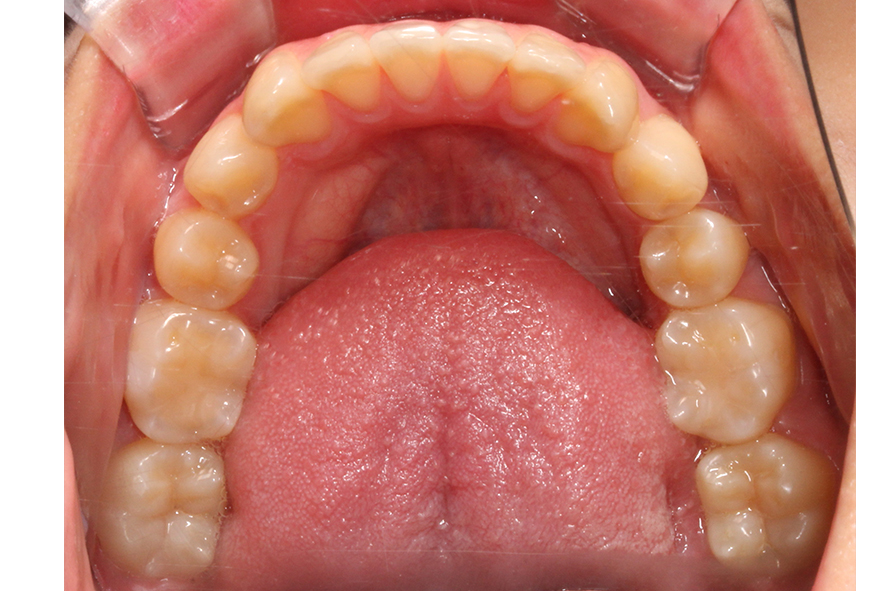

하악의 경우 상악보다 상대적으로

안모의 길이가 짧고 악궁의 길이도

길지 않은 모습입니다.

다만 치열의 정중선이 한쪽 방향으로

치우쳐져 있기 때문에 데이몬교정을 통해

안모의 정중선을 바르게 맞추어야 할 것으로 보입니다.

하악 또한 입돌출 교정 후 치열이

가지런해지고 안모의 정중선도

거의 맞춰진 모습인데요,

상악보다 악궁의 길이가

짧았기 때문에 과도한

치아의 이동은 하지 않은 모습입니다.